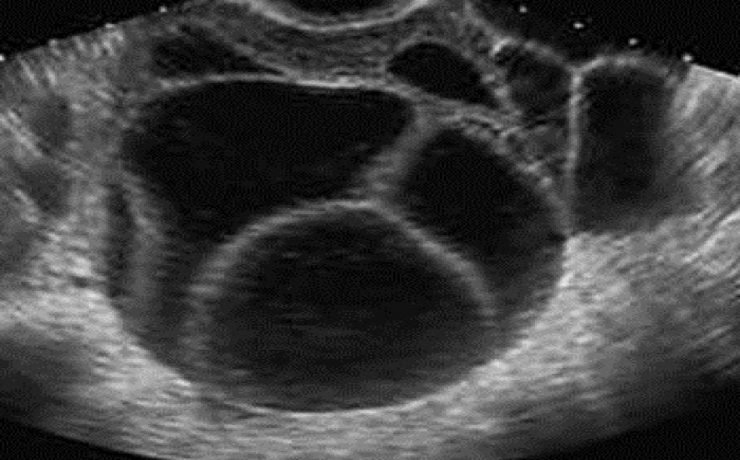

El estudio ultrasonográfico de la vía biliar requiere que el paciente este en ayunas de 6 horas, puesto que la ingesta de alimentos, sobre todo de naturaleza grasa, provoca la contracción o el colapso de la vesícula biliar, también reduce el gas intestinal que dificulta la evaluación ecográfica de la